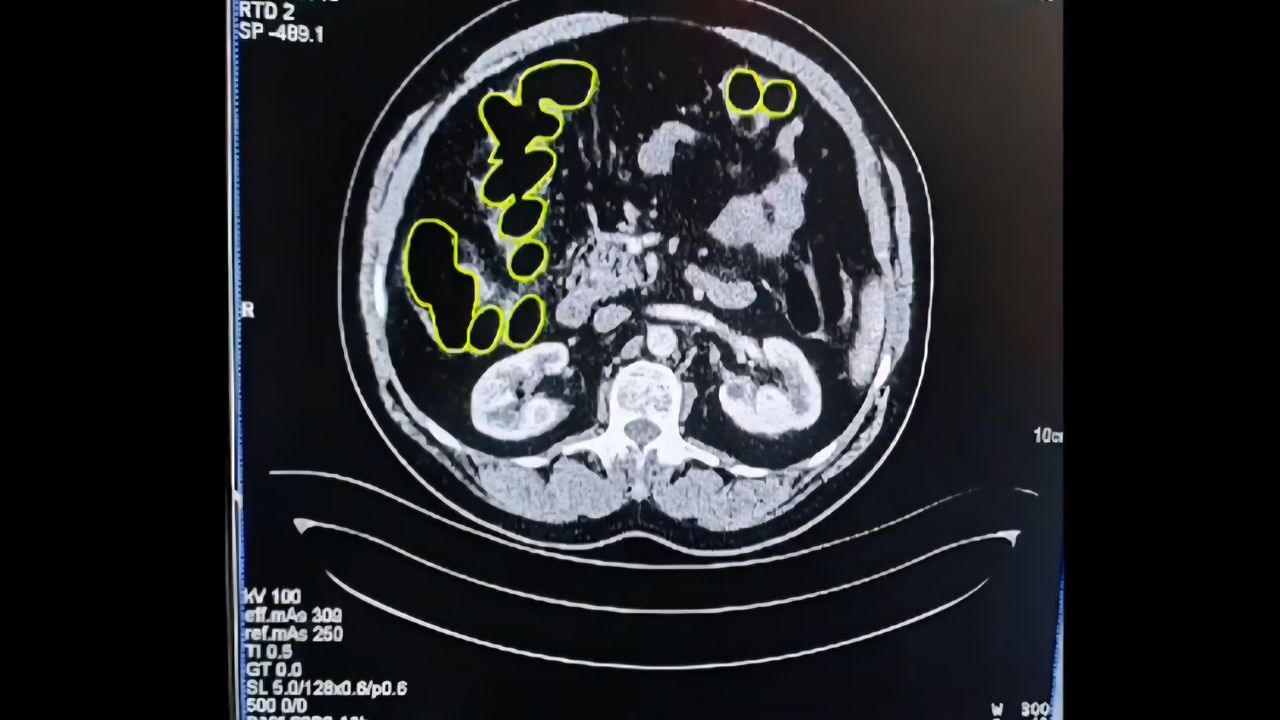

Gözaltına alınan şüpheliler, Kayseri Şehir Hastanesi’nde iç beden muayenesine alındı. Yapılan kontrollerde, mide ve bağırsaklarında çok sayıda kapsül şeklinde uyuşturucu madde bulunduğu tespit edildi.